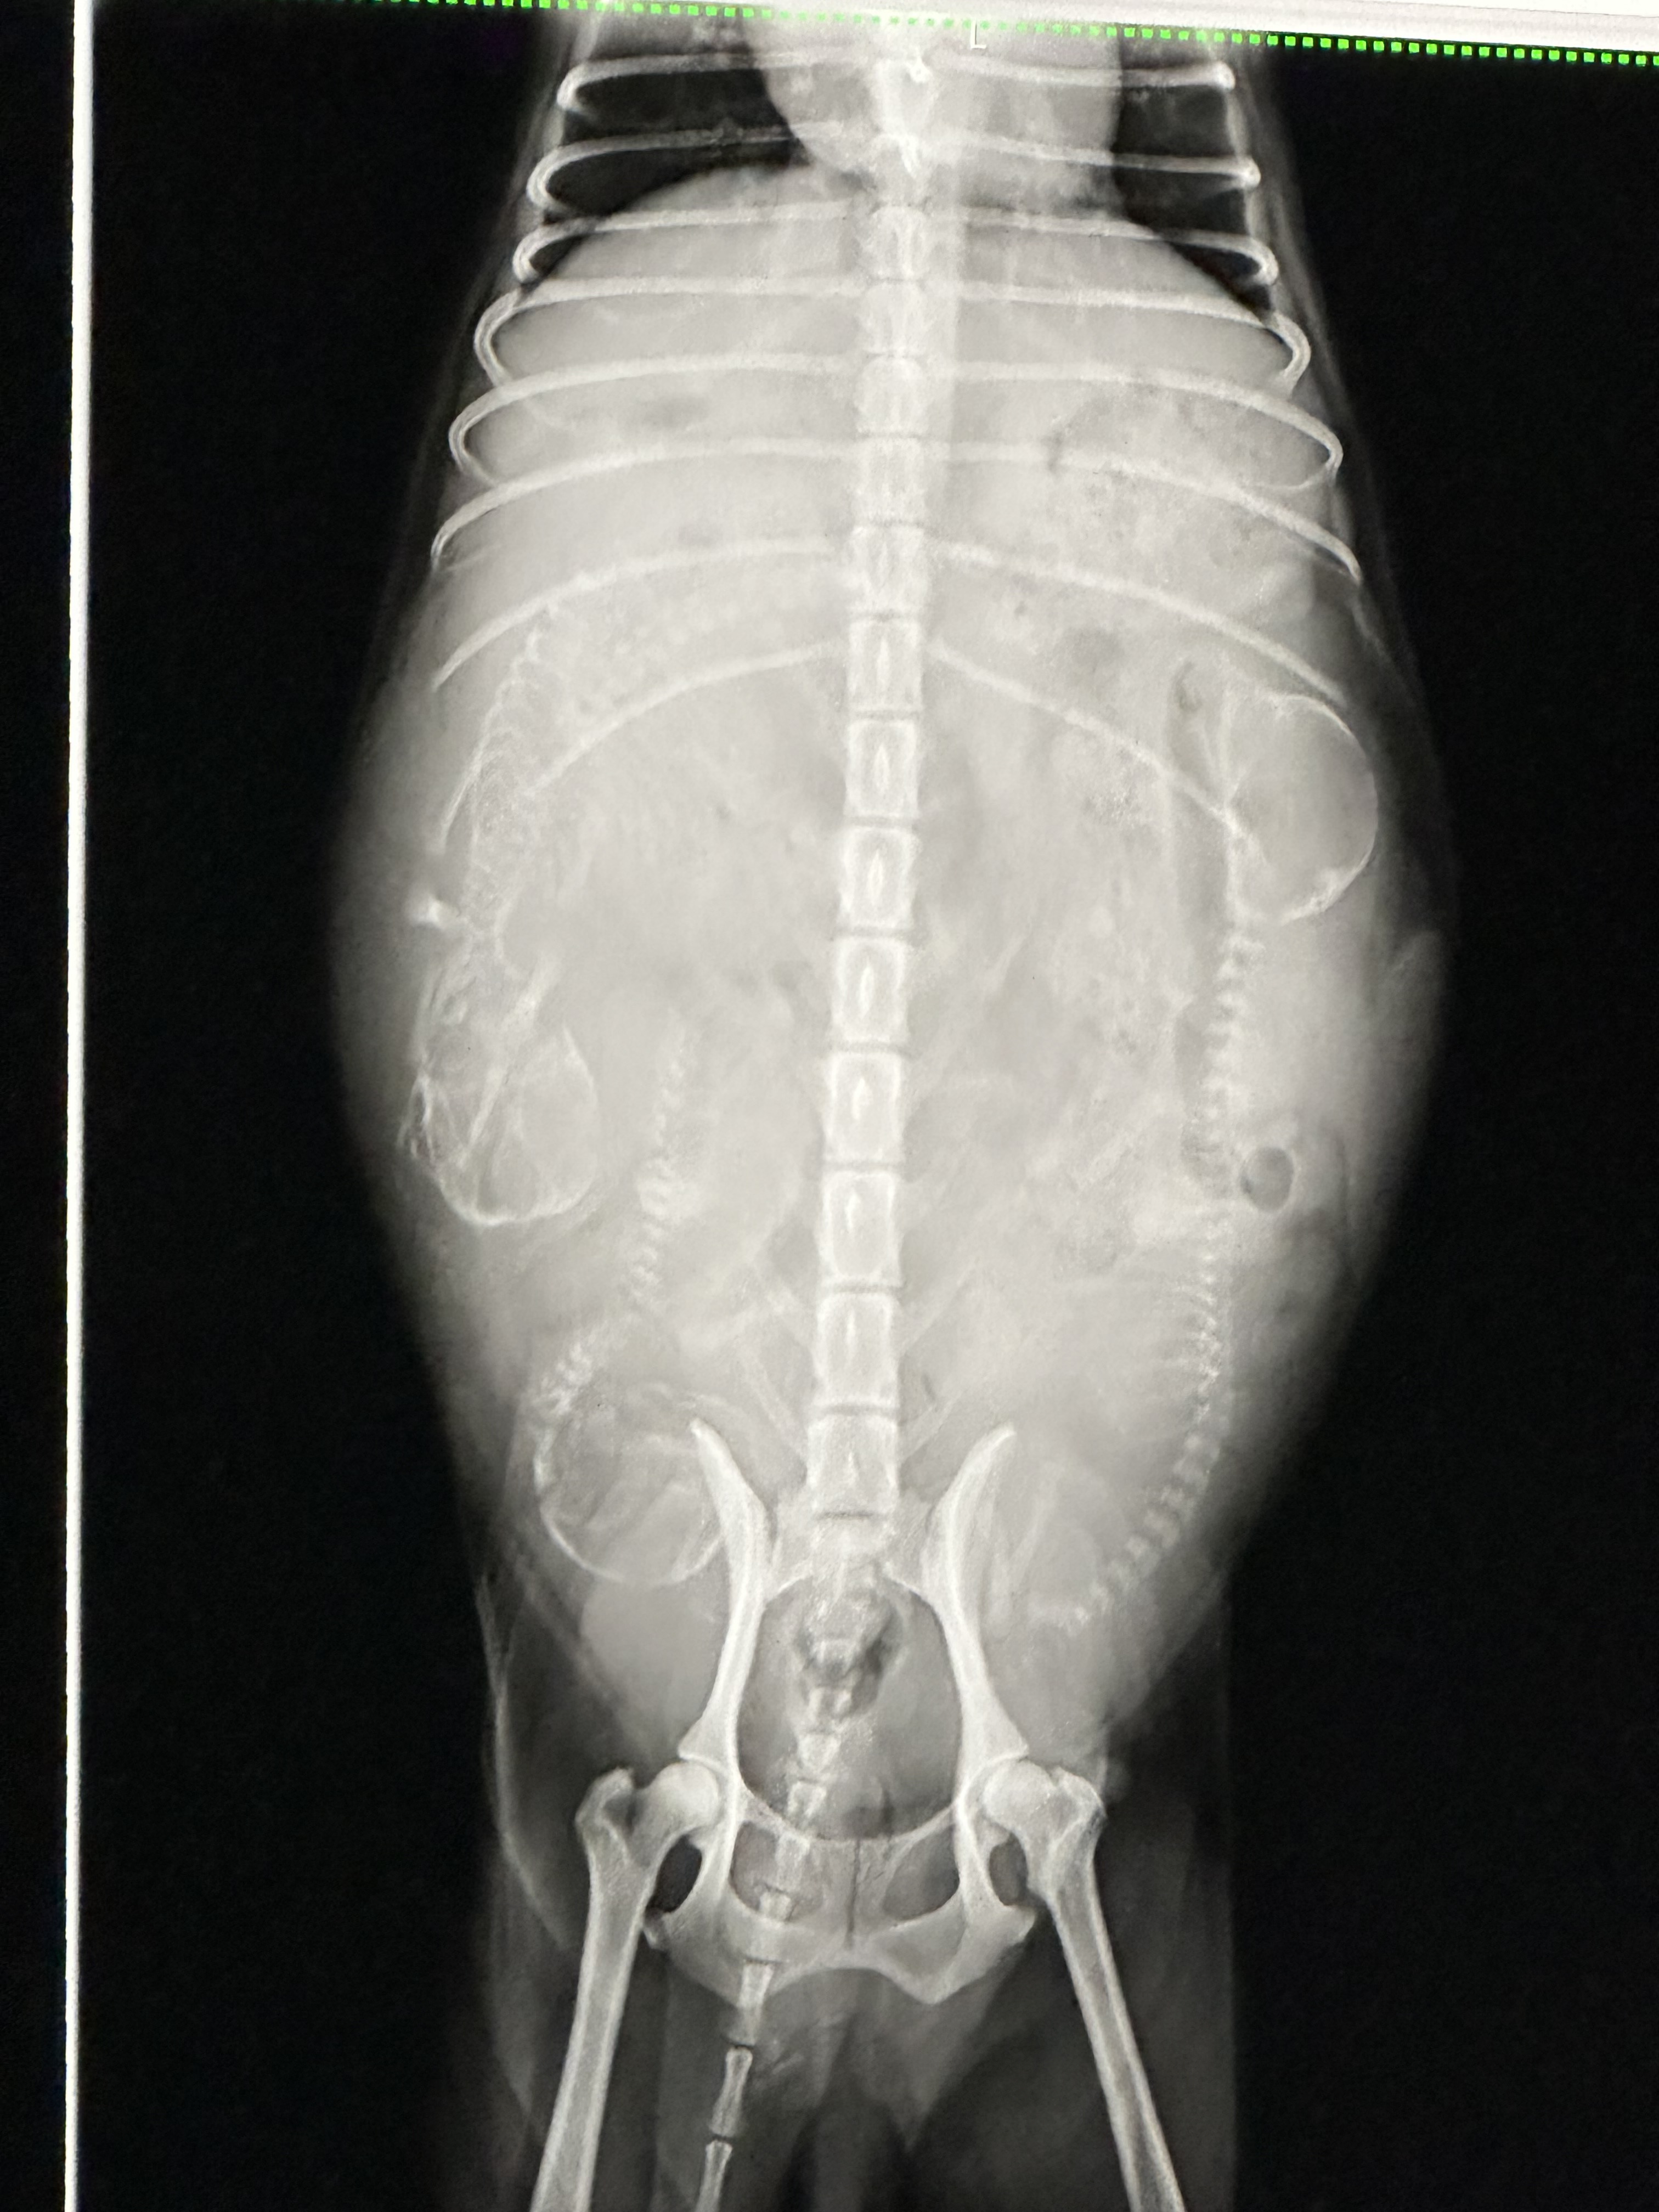

もうすぐお産を迎える六花に続き、ブラウンのメルのレントゲン検査に行ってきました。

胎児は順調に成長しており、無事にお産を迎えられそうです。